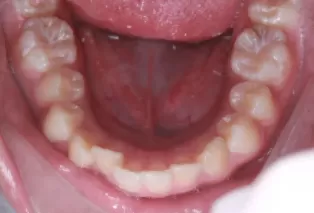

Intraoral photos